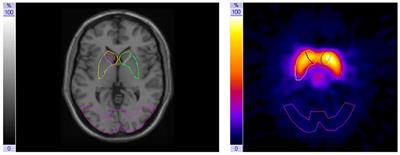

Responsivity Of The Striatal Dopamine System To Methylphenidate A Within Subject I 123 B Cit Spect Study In Male Children And Adolescents With Attention Deficit Hyperactivity Disorder Frontiers